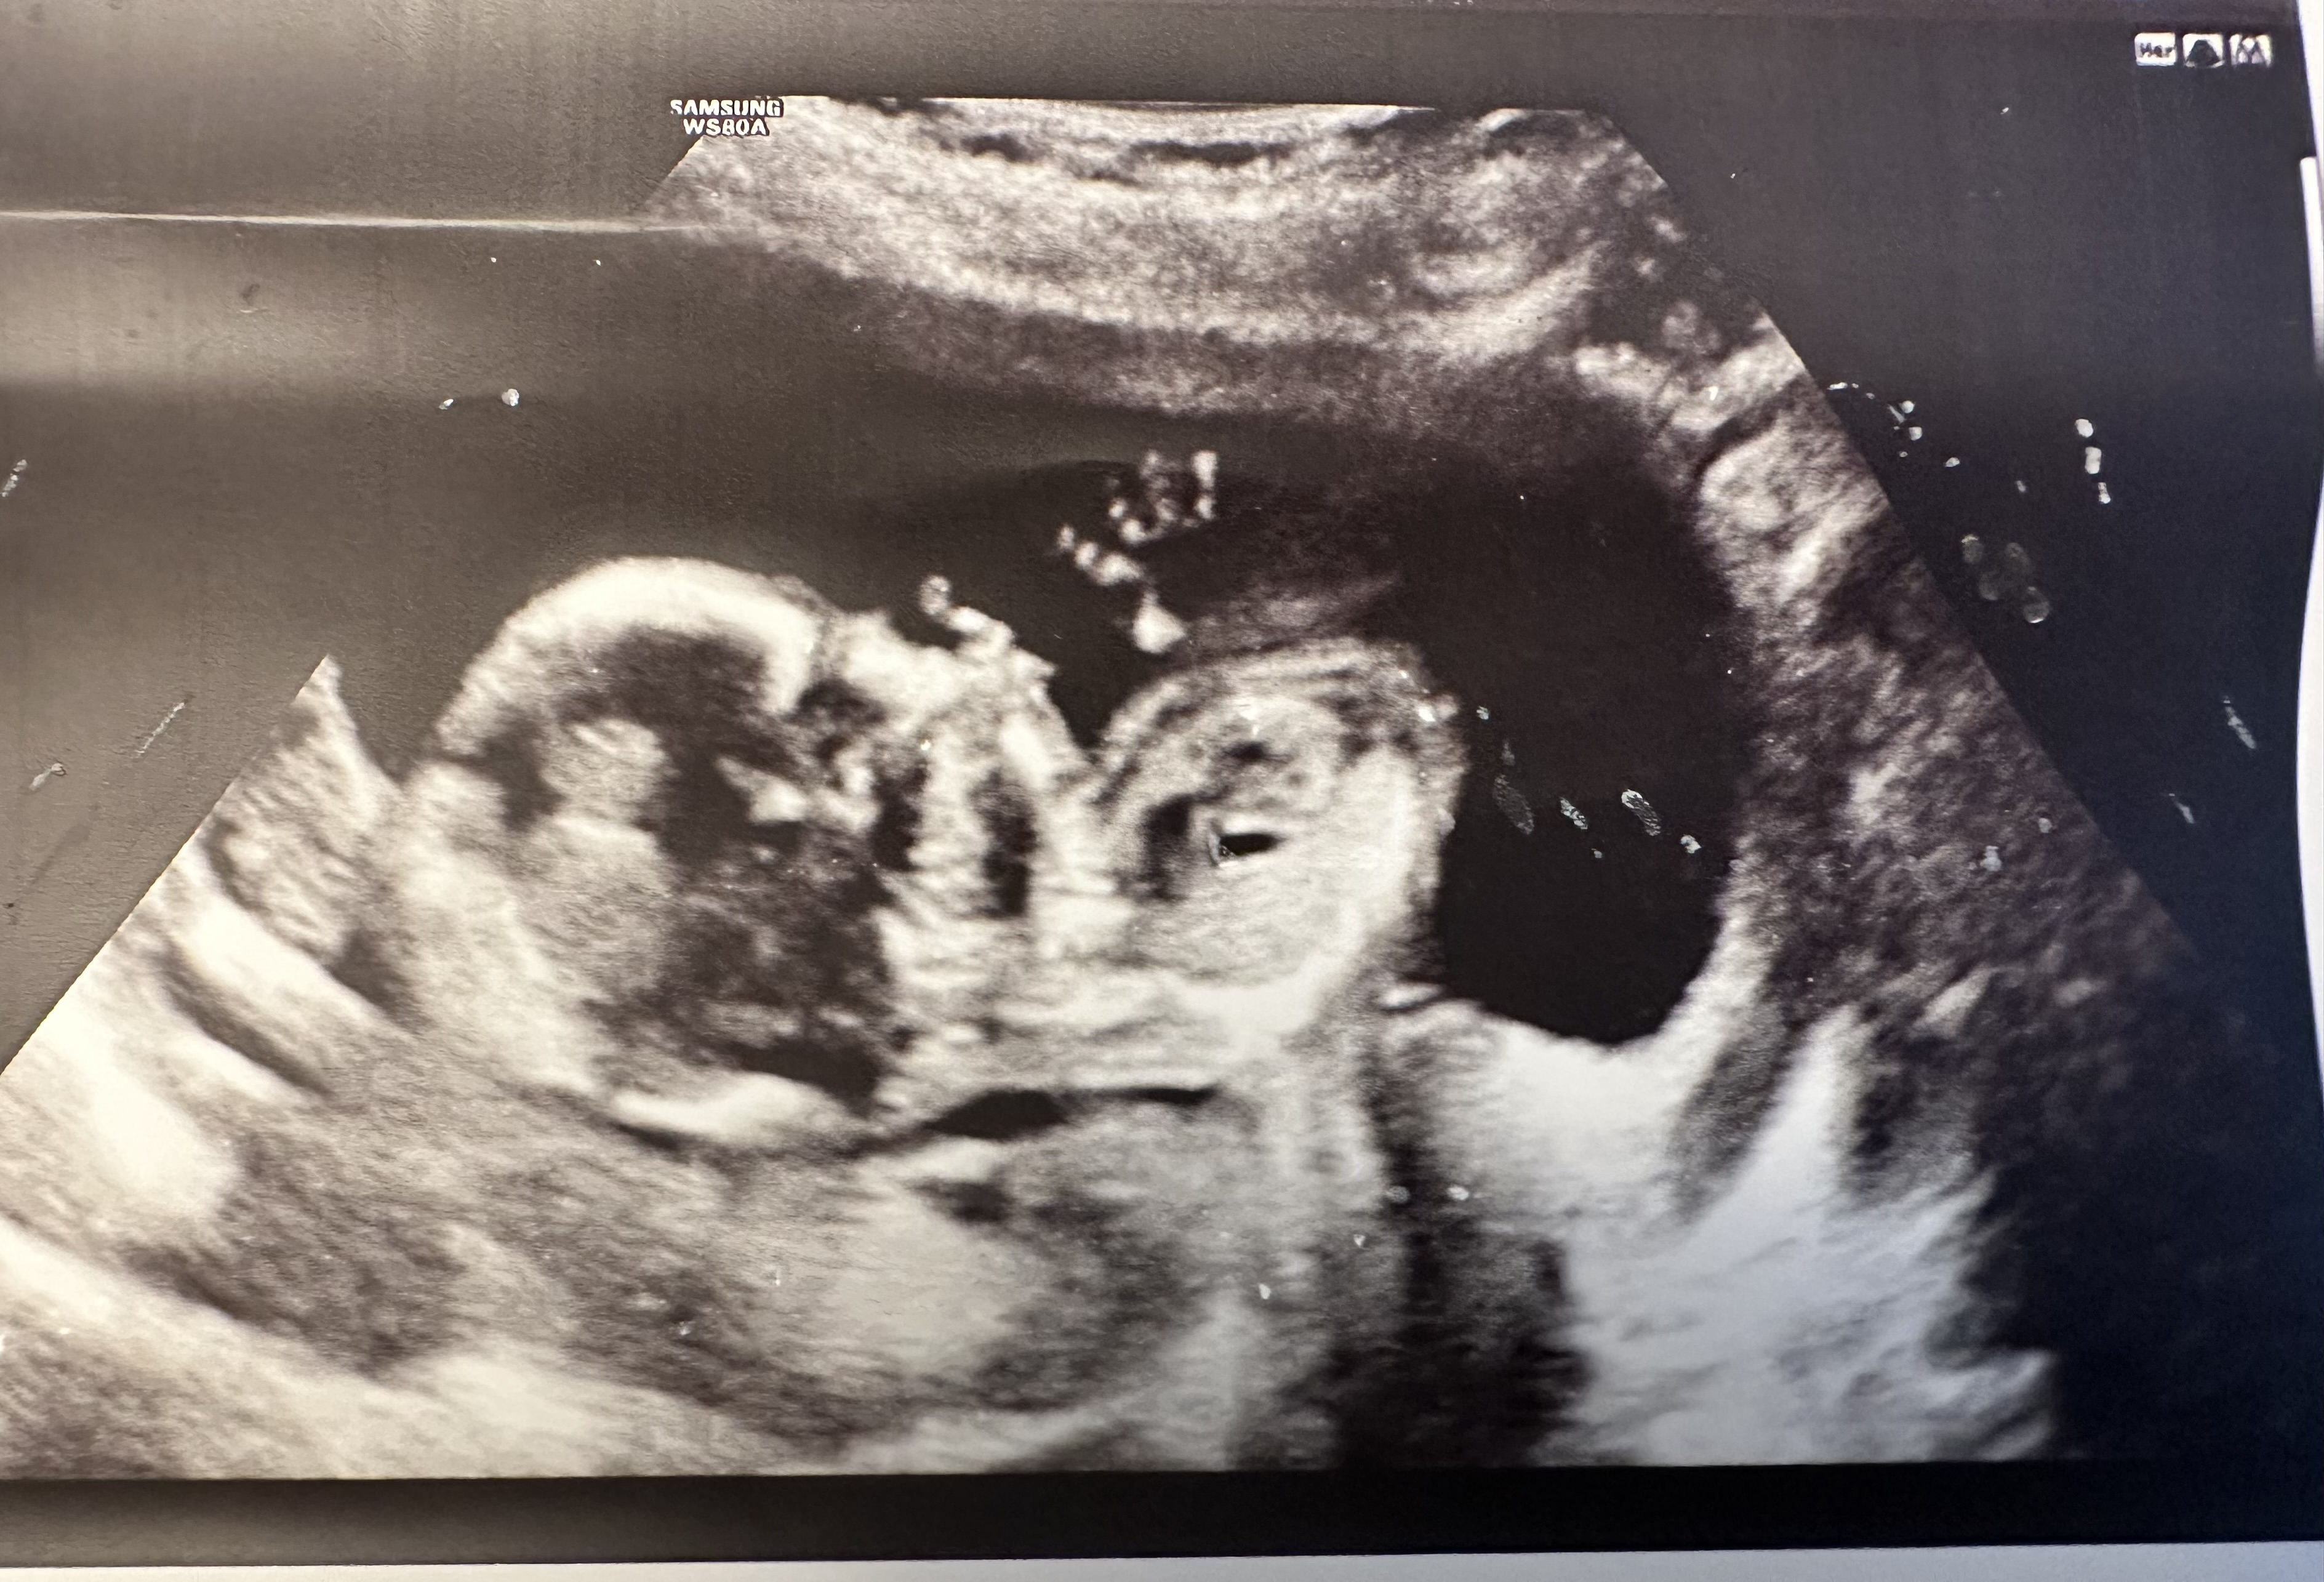

Had my anatomy scan done on Monday! They couldn’t get a good shot of baby’s face. Baby was moving around like crazy. I’ve done 5 anatomy scans before (both of my kids required me to go back for more imaging) - and I’ve never seen a baby move like this. It was wild to see! The tech was really sweet and wrote notes on the images for my kids and DH who couldn’t attend.

My sweet baby did not sit still AT ALL the entire scan. I felt so bad as the ultrasound tech was training someone and the trainee had such a hard time with my baby 😂 but anyway, here’s my sweet and very active baby boy!!!!